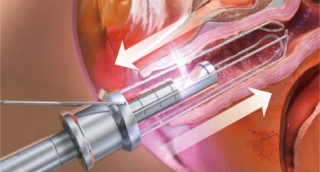

Connector

It can be rotated in a total of 8 stages

and can be rotated up to 360 degrees

Vaginal handpiece

Reflection Mirror (90°, 360°)

Gold Coated Mirror (90° Reflection)

delivers focused heat with strong energy

Handpiece Guide

It makes the same distance between tissue with laser so it guaranty the uniform laser irradiation into tissue to guaranty overall good vaginal tightening result.